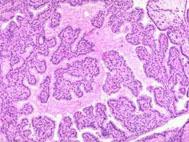

问题 腺瘤的特点有()

选项 A.可呈息肉状 B.可呈结节状 C.可呈膨胀性生长 D.可形成导管、小叶结构 E.可有纤维性包膜

答案 ABCE